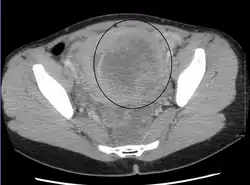

A very large (9 cm) fibroid of the uterus which is causing pelvic congestion syndrome as seen on CT -

A very large (9 cm) fibroid of the uterus which is causing pelvic congestion syndrome as seen on ultrasound -